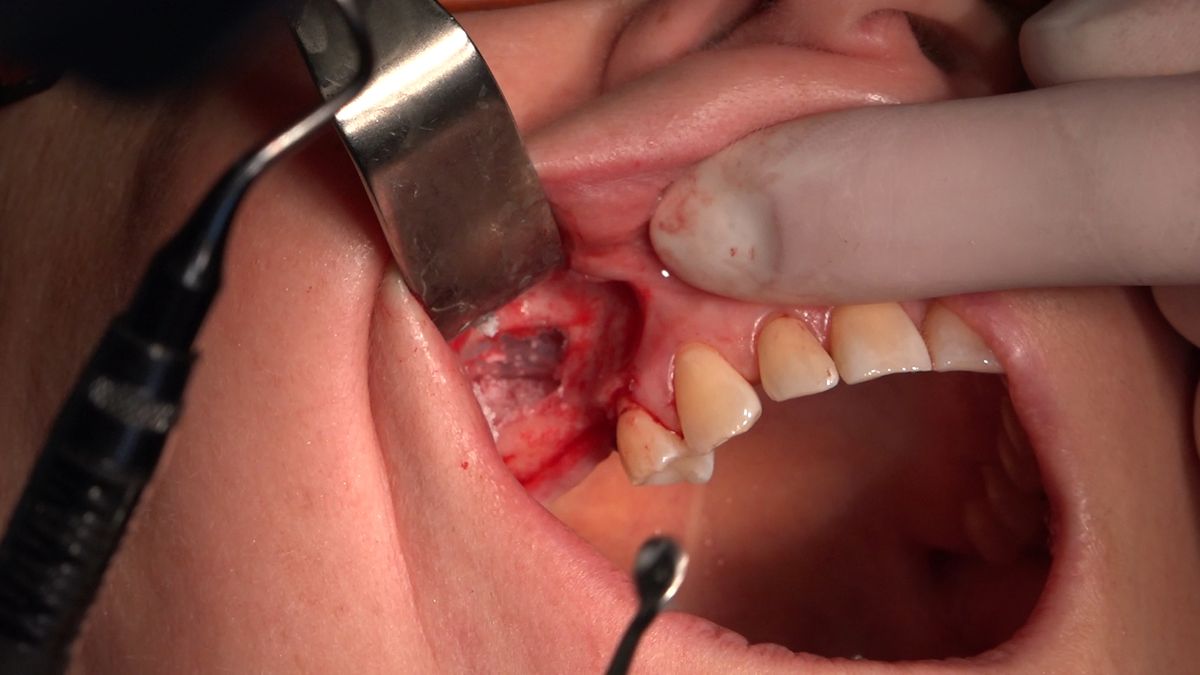

Practiculum Implantologii – Sezon VIIB, sesja 7, dzień 2